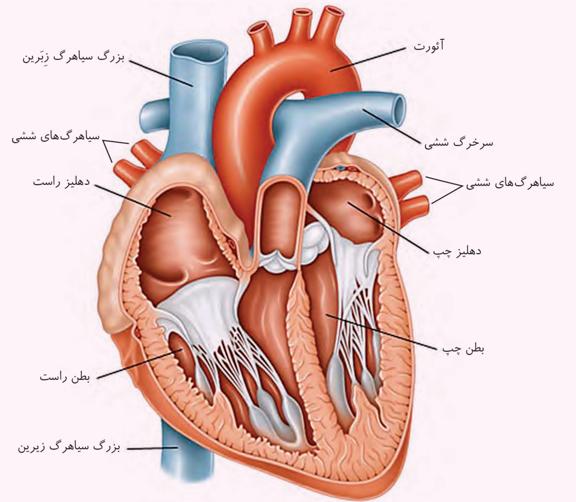

سرخرگ کلیه قبل از آن منشعب میشود. انشعابات سیاهرگی بعد از کلیه به هم میپیوندند و سیاهرگ کلیه را میسازند.

ترتیب از بالا به پایین: سرخرگ، سیاهرگ، میزنای.

سیاهرگ کلیه جلوتر از سرخرگ کلیه است.